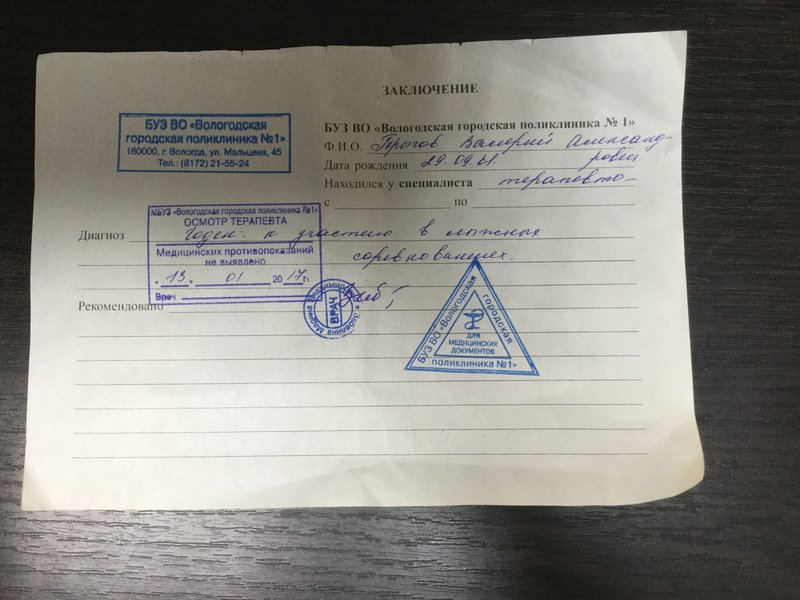

Фотографии рентгеновских снимков без необходимости направления от врача